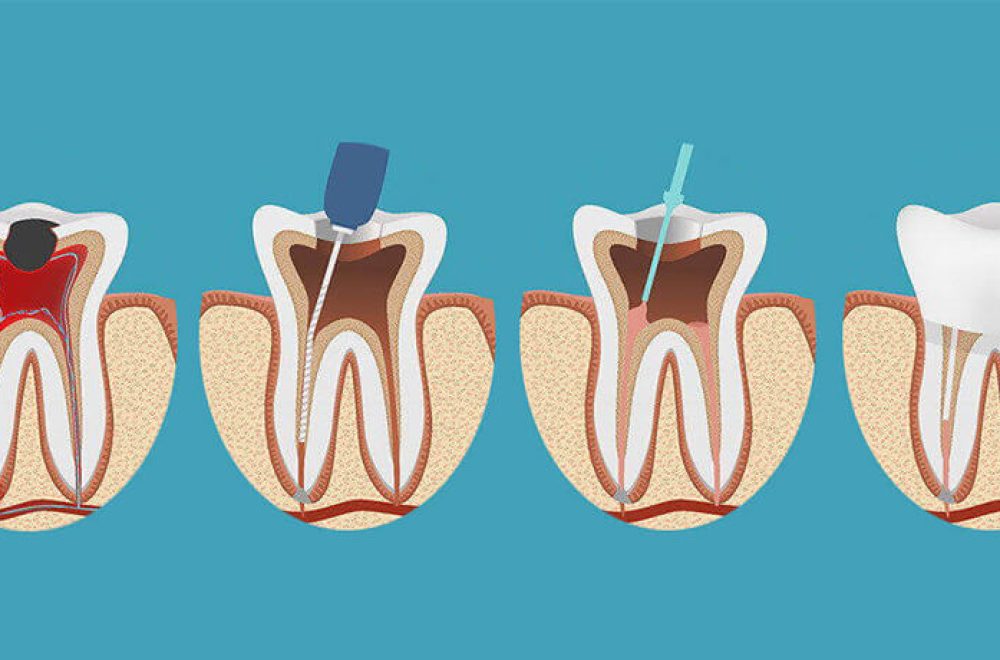

A root canal treatment is used to save a tooth that is heavily damaged, decayed, or infected. Tooth fractures, cracks in the tooth, deep cavities, facial injuries, and repeated procedures on the same tooth are all reasons that may make root canal treatment necessary. The name of this procedure comes from the cavities in the root canal of the tooth.

By removing the dental nerve and pulp (the tooth marrow) and cleaning the inside of the tooth, root canal treatment is performed to prevent infection of the surrounding tissues and prevent a dental abscess from causing more serious problems. It is important to perform root canal treatment as soon as possible to save the affected tooth and prevent tooth loss.

Root canal treatment is performed by a specialized dentist or endodontist. The first step is to take an X-ray. This X-ray is used to determine the condition of the dental canals and the presence of an infection in the surrounding tissues. Based on this, the dentist plans the root canal treatment to be performed. The second step is anesthesia.

Root canal treatment is performed under local anesthesia, which numbs the surrounding area. Anesthesia is used to numb the area near the tooth. Anaesthesia occurs in the second phase. Root canal treatment is a method of treatment performed under local anesthesia. The area near the tooth is anesthetized.

The third step is to create an opening (cavity) in the tooth. Through this opening, the affected pulp, dead nerve tissue and infected particles are removed. The inside of the tooth is completely cleaned and disinfected.

The fourth step is filling the tooth. The cavity left by the removal of pulp and nerve is filled with a special rubber material. This material, called gutta-percha, is compatible with the human body and does not cause allergic reactions. This is to avoid the risk of further infections. With this step, the root canal treatment is complete.